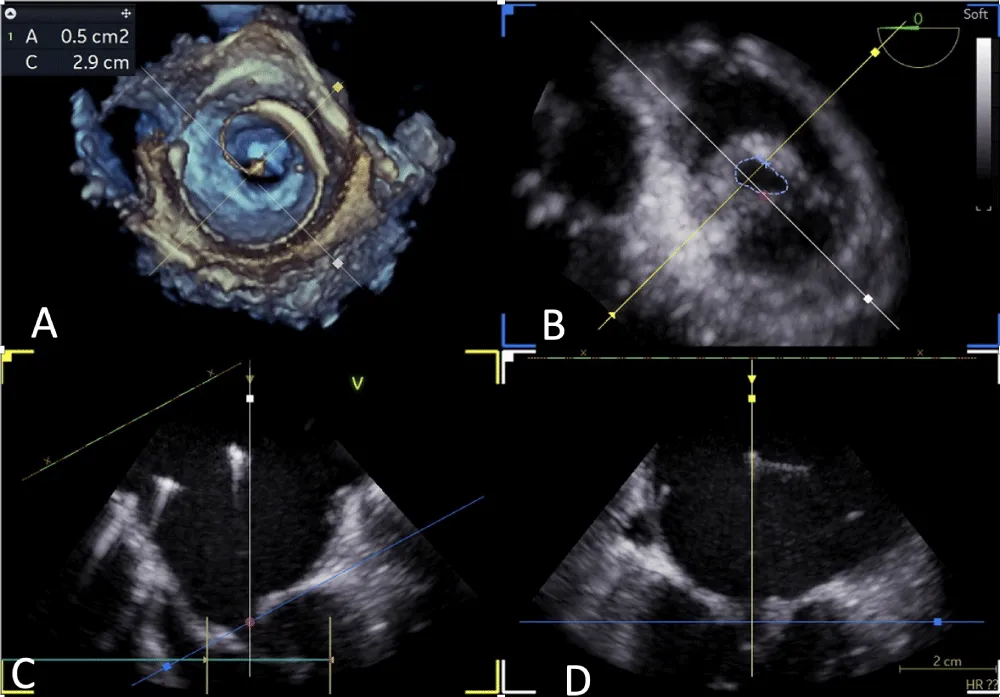

After obtaining consent, access was obtained through the right femoral vein and artery. Under 4D Transesophageal Echocardiography (4D TEE) guidance, the first transseptal puncture was performed with a broken Brough needle, and the LA wire was inserted through femoral venous access (Figure 1). Right femoral artery access was used for retrograde crossing of the aortic valve (AV) (Figure 2), and a Teflon wire was placed in the left ventricle. The aortic valve (AV) was dilated with a 14 mm ATLAS GOLD (BARD) balloon (Figure 3, Video 1).

Figure 1: A,B: 4Dimensional multiplanar transoesophageal echocardiography. A. 4D image with Left atrial wire, B. Severe mitral stenosis with mitral area of 0.5 cm2, 1C &1D. Showing multiplane of mitral valve.

Following a single dilatation, the AV gradient decreased from 82 mm Hg to 30 mm Hg without aortic regurgitation (AR). Subsequently, the mitral valve (MV) was dilated with a 26 mm Inoue balloon (Figures 4,5) (Video 2). After a single dilatation, the MV gradient was reduced from 35/21 mm Hg to 12/5 mm Hg, and the MV area increased from 0.5 cm2 to 1.6 cm2 (Figure 6)

Figure 5: 4Dimensional multiplanar transoesophageal echocardiography – Balloon dilatation of the mitral valve with Inoue balloon.

Figure 6: 4Dimensional multiplanar transoesophageal echocardiography – mitral valve after balloon dilatation.